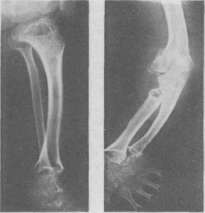

1 — атеросклероз аорты (в I косом направлении). 2— артериосклероз артерий предплечья